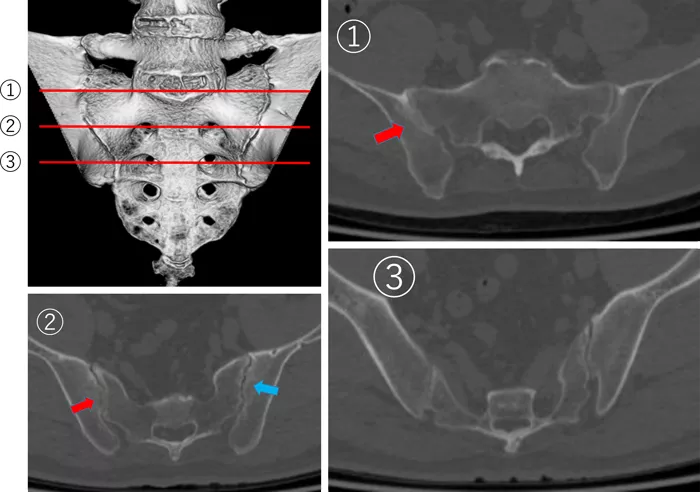

NSAIDs 内服などの対症療法を半年間行ったが、症状改善がなかったため、当科RA外来にコンサルトとなった。神経学的所見と経過より、腰椎椎間板ヘルニアと化膿性脊椎炎を否定した。また、年齢と画像所見より、DISHも否定した。再検したCRPは2.57mg/dLであり、あらためて詳細に問診と診察を行うも、炎症性背部痛を疑う症状には乏しかった。HLA検査はB39、B59であり、B27陰性であった。仙腸関節X線像を写真3に示す。右仙腸関節は3度(明らかな変化)を疑う所見であり、CT精査(写真4)にて部分的な強直を認めた。また、左仙腸関節にも骨びらんを認めた。

改訂ニューヨーク診断基準1)の臨床症状としては腰椎の可動域制限あり(Schober's test(前屈制限)は0cmで陽性)、仙腸関節のX線所見としては片側3度以上の仙腸関節炎所見ありが該当し、強直性脊椎炎の確実例と診断した。

写真4

右仙腸関節には骨性強直が一部あり(赤矢印)。

左仙腸関節には骨びらんと関節裂隙狭小あり(青矢印)。